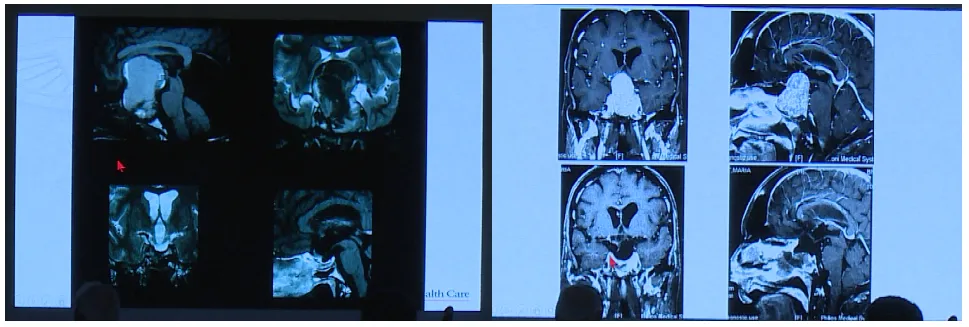

Couldwell教授演講中展示的部分巨大垂體瘤

目前巨大垂體瘤的主要治療方式為手術(shù),目的在于最大限度切除腫瘤、改善神經(jīng)功能障礙以及保留正常垂體功能。巨大垂體腺瘤術(shù)前根據(jù)影像學(xué)及臨床表現(xiàn),個(gè)體化選擇合適的入路,是成功切除腫瘤的關(guān)鍵。經(jīng)蝶入路、經(jīng)顱入路和聯(lián)合入路是切除腫瘤的可行方法。

垂體瘤從鞍內(nèi)起源,但是如果腫瘤巨大向顱內(nèi)突破了鞍隔孔,向顱內(nèi)廣泛地發(fā)展,包繞了顱內(nèi)的血管,特別是大腦中動(dòng)脈、大腦前動(dòng)脈、大腦后動(dòng)脈及其一些重要的細(xì)小分支血管。這些血管被包繞,這種情況下通常會選擇經(jīng)顱入路進(jìn)行腫瘤切除。經(jīng)顱垂體腺瘤切除術(shù)根據(jù)垂體瘤生長方向的位置可以分為三種入路途徑,經(jīng)額入路、經(jīng)硬腦膜外入路和經(jīng)翼點(diǎn)入路。